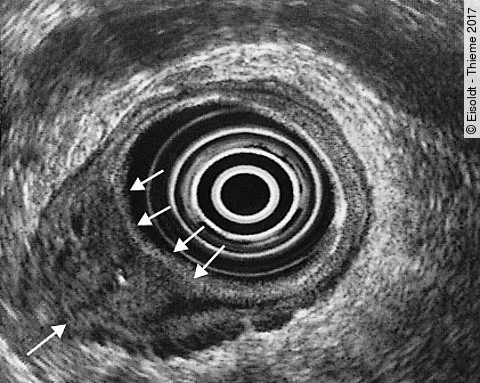

Quiz der Woche: 63-jährige Frau mit hellrotem peranalen Blutabgang

Seit einigen Wochen bemerkt die Patientin helles Blut im Stuhl. Der Tastbefund ist unauffällig, doch bei der Prokto-Rektoskopie finden Sie einen ulzerierten, blutenden Prozess.